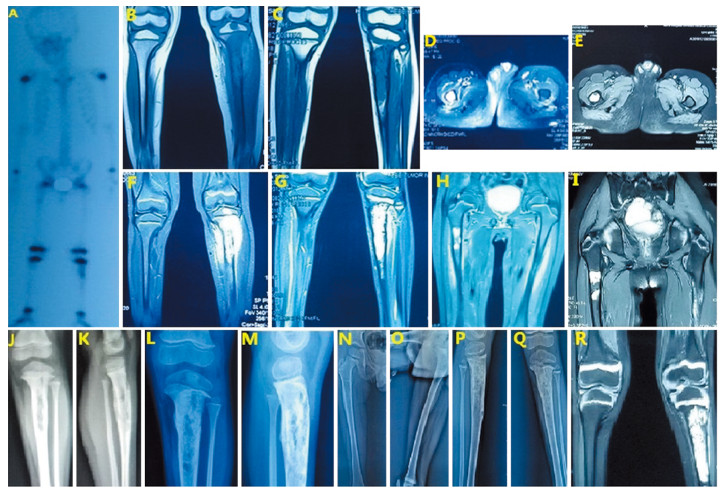

患者,男,5岁,右肾后肾腺肉瘤术后1年,因左小腿近段疼痛1月,于2017年8月17日收入我院骨科。入院前1月患儿出现左侧小腿近段疼痛,1周前加重并出现跛行,行患肢X线检查,发现胫骨近端占位,遂入院治疗。既往患者因“右肾占位”于2016年8月16日于我院泌尿外科行右肾根治性切除术,见图 1。病理:瘤细胞形态一致,呈管状、腺泡状排列。间质呈无细胞的水肿样、黏液样或者玻璃样变的状态,免疫组织化学结果:CK(-)、Vim(+)、CD34(-)、CD99(+)、WT1(-)、Ki-67(阳性细胞数40%)、S100(-)、Des(-)、EMA(-)、Act(-)、Myo(-),后肾腺肉瘤,见图 2。术后患者未行后续治疗。入院查体:左小腿近端压痛,明显肿胀,胫骨结节水平周径较对侧增粗2 cm,膝关节屈伸活动正常。全身骨扫描示:右股骨上段可见异常核素浓聚,相应部位髓腔内见片状低密度及高密度影,左胫骨上段可见异常核素浓聚,相应部位骨皮质破坏伴周围软组织包块形成,见图 3A。膝关节及胫腓骨CT示左侧胫骨近中段骨质破坏。MRI示:胫腓骨近中段见不规则T1稍高信号,T2高信号影,胫骨近段骨皮质不连续,周围软组织内可见不规则T1稍高信号,T2高信号影,见图 3B、F。胸腹部CT未见局部复发及肺、肝等内脏转移征象。患者入院后为明确病变性质及来源,于2017年8月23日行左胫骨病变切取活检术,术中刮取髓腔病变呈“鱼肉样”肿瘤组织送检。病理示:破碎灰白质韧组织一堆,直径1 cm。区域瘤细胞小圆形,在幼稚的黏液间质中弥漫性分布,部分呈梭形;无病理性核分裂相;无坏死。免疫组织化学检测示:CK(-),WT1(-),Vim(+),Ki-67(阳性细胞数50%),Desmin(-),SMA(+/-),CD34(血管+),S100(-)。少许间叶源性恶性肿瘤,对比既往右肾肿瘤病理,符合后肾腺肉瘤骨转移,见图 2。于2017年9月起给予AI方案(ADM 60 mg/m2+IFO 8 g/m2,21天为一疗程)化疗3周期,其中第2周期化疗结束出现Ⅳ度粒细胞缺乏伴粒细胞缺乏性发热,经G-CSF、预防应用抗生素后体温及白细胞数量逐渐恢复正常,第3周期化疗给予减量25%后仍再次出现Ⅳ度骨髓抑制、粒细胞缺乏。化疗结束后查体显示左小腿肿胀较化疗前明显减轻,胫骨结节水平周径较对侧增粗0.5 cm。复查胫腓骨X线示病变较前好转,MRI提示软组织包块明显缩小,髓腔内病灶未见明显变化,见图 3C、G。对侧股骨近端转移灶未见明显变化。因患者家属拒绝继续化疗,2018年1月起改用甲磺酸阿帕替尼每日250 mg维持,并继续每3月随访,病情持续控制稳定。至2018年9月患儿突发右侧大腿近端肿胀、疼痛,复查发现右股骨近端髓腔内异常信号,伴股骨干周围异常信号,左侧胫骨近端病变较前无明显变化,见图 3D、H,骨扫描提示右股骨核素浓聚范围较前增大,左胫骨近端核素浓聚较前无明显变化。考虑病情较前进展,病情评估PD,患儿家属拒绝进一步化疗,遂于2018年9月后每4周加用一次唑来膦酸1 mg静滴,患儿耐受性良好,无发热等不良反应,肝肾功能无异常,至2018年12月末次复查MRI见左侧胫骨近端病变无明显变化、右侧股骨近端髓腔内病变无变化、股骨干周围异常信号消失。查体右侧大腿近端肿胀较前明显消退,周径与对侧大腿同水平相等。病情评估PR,患者未出现异常反应,末次随访MRI显示左侧胫骨近端转移灶及对侧股骨近端转移灶未见明显变化,见图 3E、I、R,目前患者病情变化仍在进一步随访中。

![]() 图 3 患者术后骨转移灶影像学图片Figure 3 Imaging of bone metastases in the patient after nephrectomyA: whole body bone scan, 2017-9; B, F: tibiofibula MRI, 2017-9; J, K: left tibiofibula X-ray, 2017-9; C, G: tibiofibula MRI after chemotherapy, 2018-1; L, M: left tibiofibula X-ray, 2018-1; D, H: later femoral MRI after 8 months of apatinib treatment, 2018-9; E, I, R: MRI after 4 months of apatinib+zoledronic acid, 2018-12; N, O, P, Q: X-ray after 4 months of apatinib + zoledronic acid, 2018-12

图 3 患者术后骨转移灶影像学图片Figure 3 Imaging of bone metastases in the patient after nephrectomyA: whole body bone scan, 2017-9; B, F: tibiofibula MRI, 2017-9; J, K: left tibiofibula X-ray, 2017-9; C, G: tibiofibula MRI after chemotherapy, 2018-1; L, M: left tibiofibula X-ray, 2018-1; D, H: later femoral MRI after 8 months of apatinib treatment, 2018-9; E, I, R: MRI after 4 months of apatinib+zoledronic acid, 2018-12; N, O, P, Q: X-ray after 4 months of apatinib + zoledronic acid, 2018-122 讨论